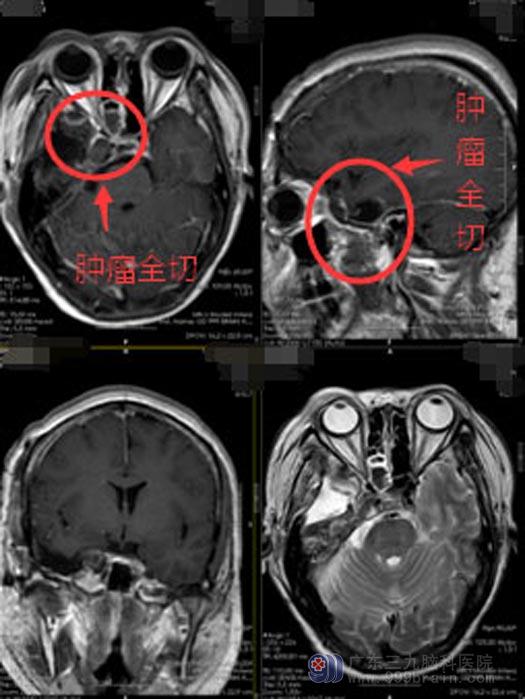

订制了严谨周密的治疗方案后,由鲁明主刀为小静实施“右侧鞍旁-海绵窦内神经鞘瘤切除术”。术中出血少,肿瘤被全部切除。目前已顺利出院。